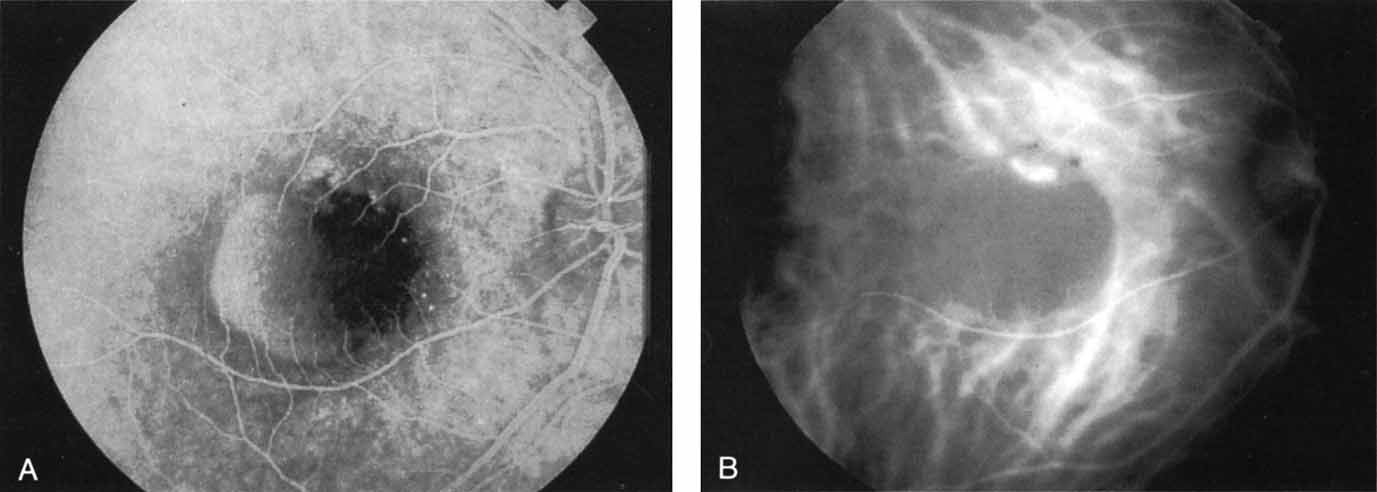

In acute multifocal posterior placoid pigment epitheliopathy, discrete hypofluorescent geographic areas are present both in the posterior pole and extending into the mid-periphery on ICG angiography65,66 (Fig. 16). These hypofluorescent areas are more extensive than noted on either clinical or fluorescein angiographic examination. They are noted in the early phases of the ICG study and persist late, suggesting that ischemic changes in the choroidal circulation occur in this disease. The hypofluorescence remains even once lesions have healed.

Fig. 16 A. Clinical photograph of a patient with acute multifocal placoid pigment epitheliopathy (AMPPE). There is extensive involvement of the central macula by the inflammatory lesions. B. Late-phase indocyanine green angiogram demonstrating extensive confluent but irregular areas of marked hypofluorescence. The hypofluorescence in AMPPE is believed to represent a perfusion abnormality within the choroidal circulation.